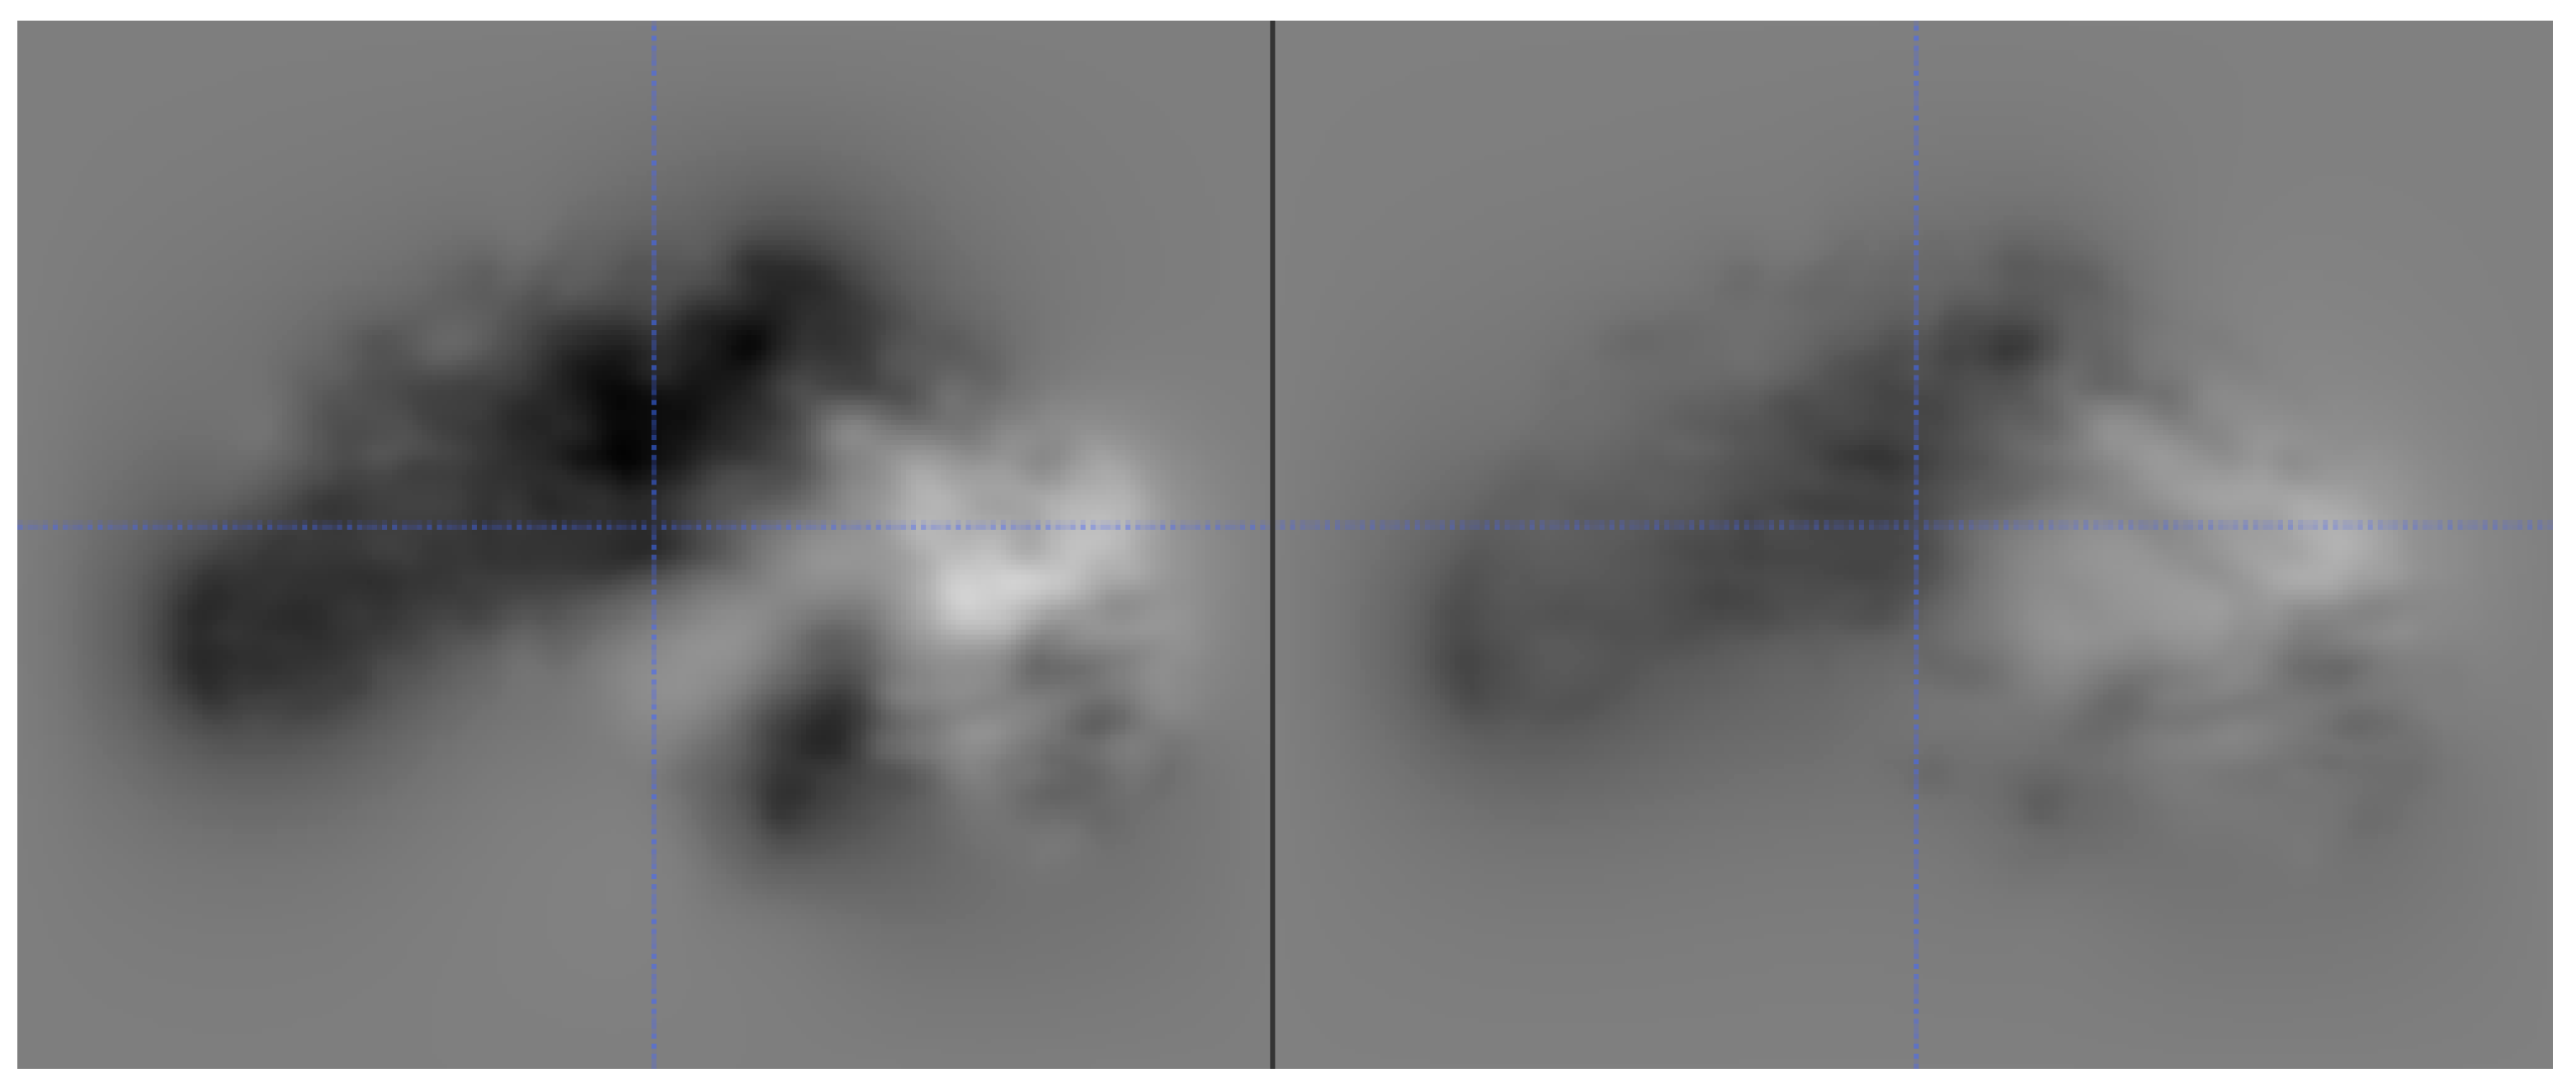

4.2.2. Deformation Field

Apart from the two main intensity-based similarity metrics described above, we also computed the norm of all displacement vectors of the deformation field after registration of the original image and the corresponding reconstruction to assess the success of the inversion attack. Therefore, we affinely registered each reconstructed image to the true original image and all other original images of the database using ANTs [25] and mutual information as the similarity measure. In the second phase, each affine registration was further refined using a non-linear registration optimized using the cross-correlation similarity measure implemented in ANTs. In this case, it is assumed that the norm of all displacement vectors of the deformation field should be smallest for the true original image of a reconstruction when compared to the corresponding values for all other images. Exemplary deformations are shown in Figure 7. Using this approach, the mean rank (for skull-stripped images) of the true original image is for the U-net, as well as SegNet. More precisely, 24 reconstructed datasets could be accurately matched to the true original image for the U-Net, while 22 datasets could be matched correctly for the SegNet reconstructions.

Figure 7.

An example of a good reconstruction (left), which has much smaller, and more localized deformations compared to an example of a bad reconstruction (right), which requires large deformations everywhere. Smaller deformations are displayed by the darker intensities, while the larger deformations are displayed by lighter intensities.